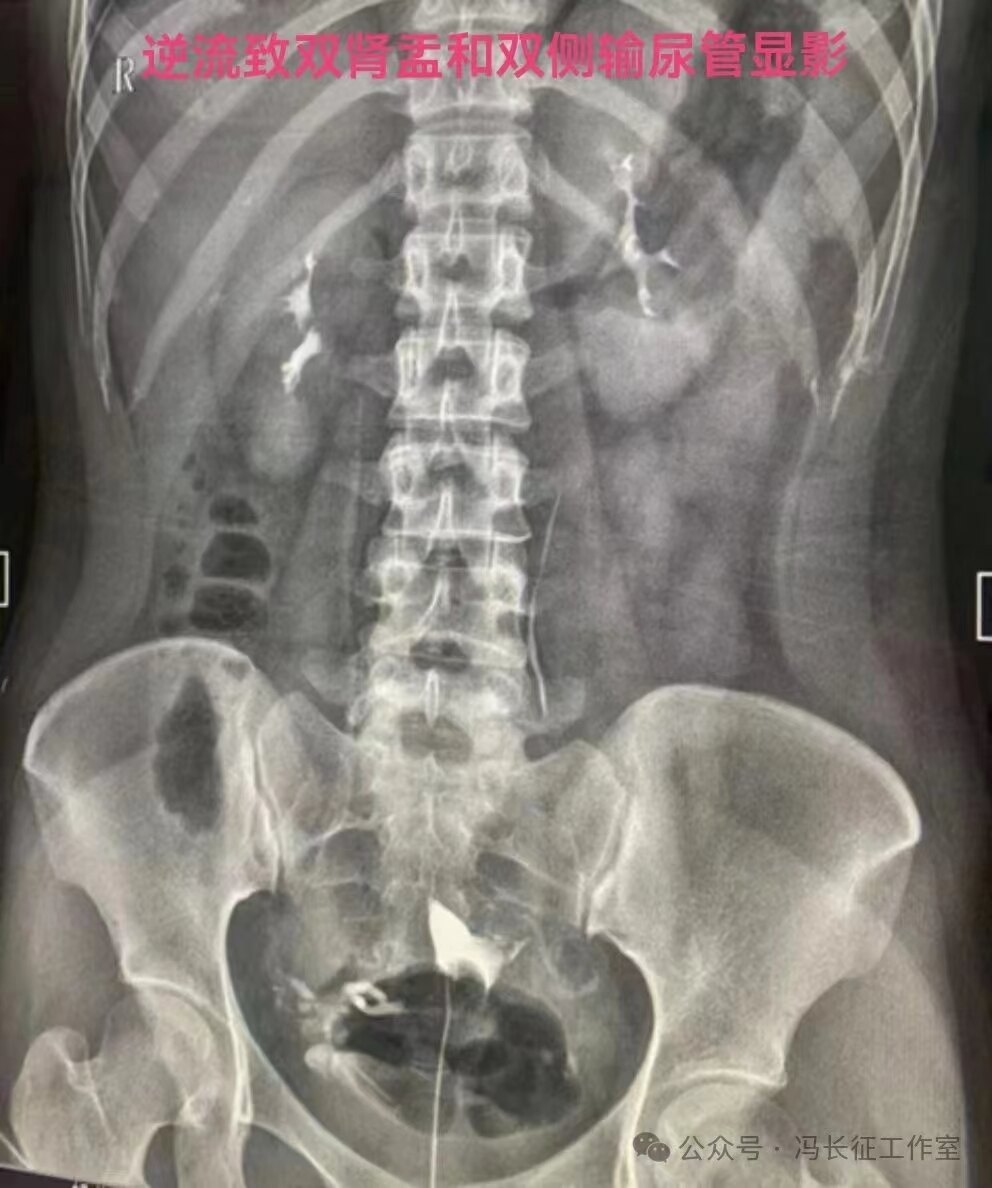

在子宫输卵管造影,用碘油做造影剂当出现逆流时立即停止造影检查,避免更多碘油进入静脉造成肺栓塞是正确的。但是,当用的造影剂是碘水时,出现逆流时还是可以继续进行造影检查,最终完成造影检查,尽量给被检查者一个完整的检查。千万不要听所谓的砖家乱讲,当发现有造影剂进入间质或血管,应立即停止造影。我们大家都知道成人在做CT增强检查时,常规用高压注射器直接从静脉注入约100毫升含碘水剂进行检查几十年了,因此,碘水是可以进入静脉和淋巴的。一般子宫输卵管造影所用含碘水剂20毫升左右,即使20毫升含碘水剂都逆流静脉不会对身体有啥影响的。因为含碘水剂主要经肾从尿液排出体外,有时还相当于免费送一个静脉肾盂造影检查。

造影剂逆流可以进入静脉和淋巴管,逆流分三种:(1)淋巴逆流;(2)静脉逆流;(3)淋巴和静脉混合性逆流。其实,一般多是静脉和淋巴都有的混合性逆流,淋巴逆流是造影当时以淋巴逆流为主,同时有少量的静脉逆流,本来淋巴管后来就是要汇入到静脉的。静脉逆流也是以静脉逆流为主,同时有少量的淋巴逆流。

一定要知其然,也要知其所以然。切记!切记!当子宫输卵管造影检查所用的造影剂是碘水时,出现逆流时还是可以继续进行造影检查,最终完成造影检查的。